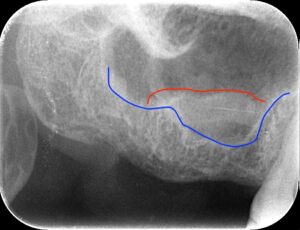

この場合も残っている骨が少ないです。

この場合は段階法を選択し人工骨のみを

入れました。赤線より下が人工骨を足した部分です。

その後インプラントを埋入しました。